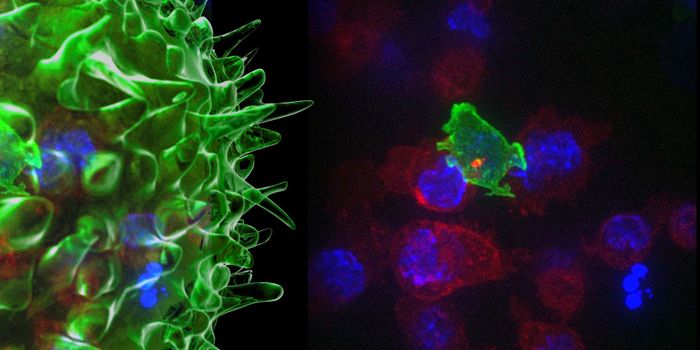

MAY 21, 2019Cell & Molecular BiologyScientists have visualized how the body tests out important defensive cells, and have captured the process on video.